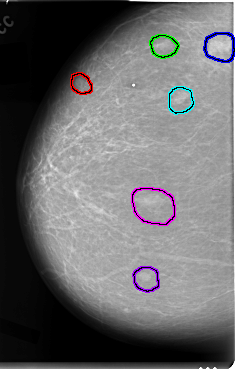

C_0025_1.LEFT_MLO

FILE: C_0025_1.RIGHT_MLO.OVERLAY

TOTAL_ABNORMALITIES 6

ABNORMALITY 1

LESION_TYPE MASS SHAPE ROUND MARGINS CIRCUMSCRIBED

ASSESSMENT 2

SUBTLETY 5

PATHOLOGY BENIGN

ABNORMALITY 2

ABNORMALITY 3

ABNORMALITY 4

ABNORMALITY 5

ABNORMALITY 6

RIGHT_MLO LINES 5896 PIXELS_PER_LINE 3880 BITS_PER_PIXEL 12 RESOLUTION 50 OVERLAY